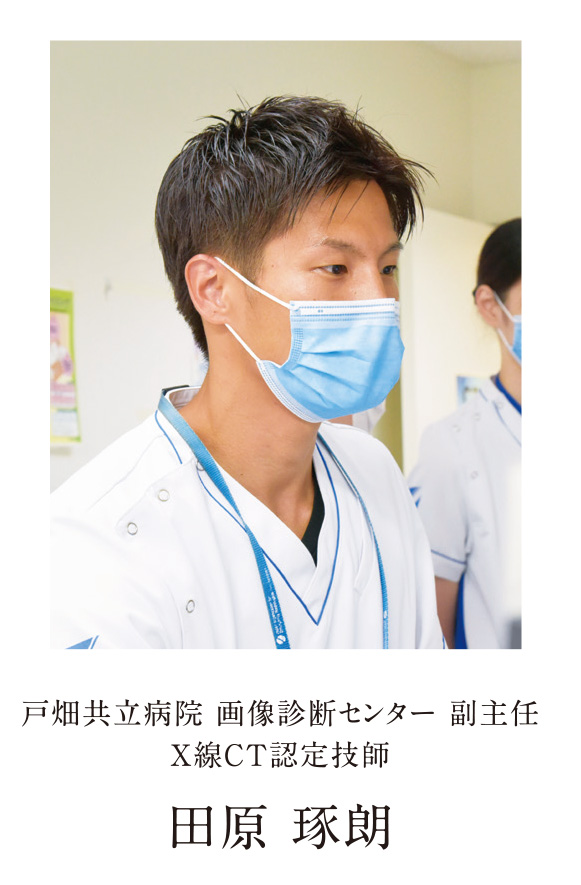

認定看護師・技師からのmessage ~伝えたいこと~ Vol.11

飛躍的に進化したCT検査

皆さん、CT検査の画像を見たことはありますか?CT画像はよく「体の輪切り画像」と表現されます。近年のCT装置の進歩は著しく、専門的な画像処理を施すことで「輪切り画像」だけでなく、様々な画像表示を行うことができるようになりました。上に示すのはほんの一例ですが、「3D画像」といって患者さまに疾患を説明する際や手術の前に綿密なシミュレーションを行う際に役立つものです。白黒のCT画像を用いて作成するのですが、色付けをすることで誰にでも疾患を理解しやすい画像となっていますこのように、現代の医療において患者様の病気を早期発見し、安心して安全に治療を受けていただく上でCT検査は必要不可欠となっています。

皆さん、CT検査の画像を見たことはありますか?CT画像はよく「体の輪切り画像」と表現されます。近年のCT装置の進歩は著しく、専門的な画像処理を施すことで「輪切り画像」だけでなく、様々な画像表示を行うことができるようになりました。上に示すのはほんの一例ですが、「3D画像」といって患者さまに疾患を説明する際や手術の前に綿密なシミュレーションを行う際に役立つものです。白黒のCT画像を用いて作成するのですが、色付けをすることで誰にでも疾患を理解しやすい画像となっていますこのように、現代の医療において患者様の病気を早期発見し、安心して安全に治療を受けていただく上でCT検査は必要不可欠となっています。

一方で、CT検査というと被ばく線量に関して不安を抱く方もいるかと思います。CT検査で受ける被ばく線量は微量であり、過度に心配する必要はありませんが、少しでも少ない被ばく線量で検査を受けたいと思うのが患者様の心理だと思います。そこで、私たちX線CT認定技師は、日額の線量を管理しつつ、患者様の疾患や治療法などに合わせて最適な検査を提供できるように、日々更新される最新技術の獲得やその有用性などを専門的に評価しています。私たちは複雑化した技術への対応を図りながらCT検査を実施し、様々な形でCT画像を提供することにより、患者様に寄り添うCT検査を目指しています。